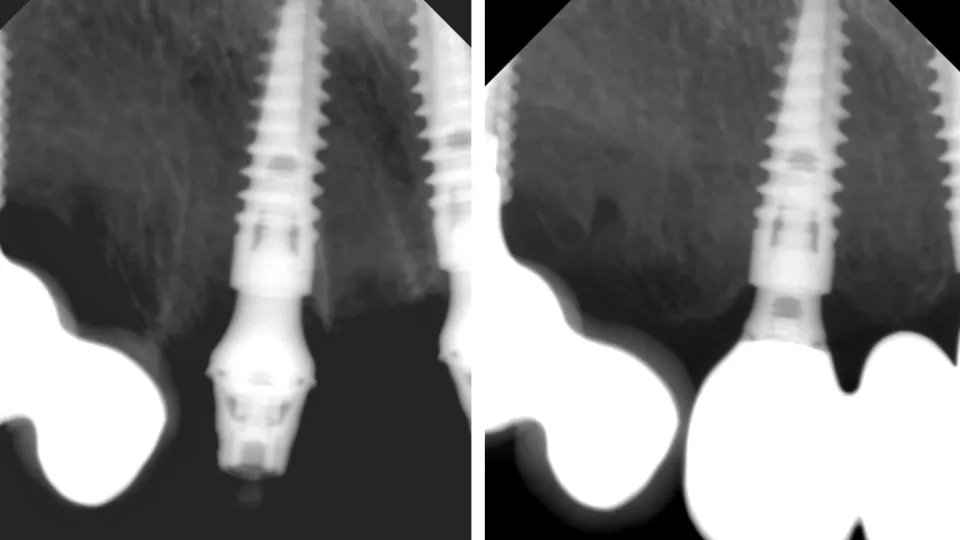

Сравнительная рентгенограмма этого клинического случая с протезированием с уровня MultiUnit абатмента (снимок слева) и с уровня MedentiBase абатмента (снимок справа) (Илл. 59).